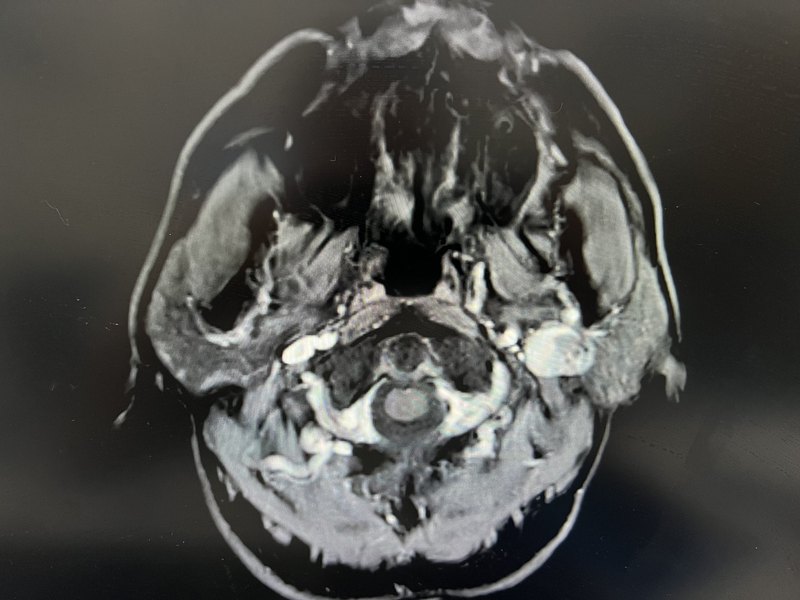

腮腺腺泡細胞癌(Acinic?cell?carcinama)是臨床比較少見的一種惡性腫瘤。約占唾液腺腫瘤的3%左右,男女發(fā)病比例約3:1。臨床具有如下特點:1)?好發(fā)于腮腺淺葉,多為單側發(fā)病,患者常有較長的病史;2)?多為無痛性腫塊,淋巴結轉移率低,約為3%~9%。3)?大部分腫瘤具有包膜,與周圍正常腮腺組織分界尚清晰,故容易與腮腺良性腫瘤混淆。4)?CT上腫瘤呈稍低密度或等密度,鈣化少見;MRI上病灶呈等T1、混雜長T2信號,密度、信號多不均勻。治療上,臨床根據腫瘤的位置決定手術方式,位于淺葉者,行腮腺淺葉全切除+面神經解剖術;如位于深葉則應行腮腺全切除術,如腫瘤侵犯面神經,受累的神經應一并切除并行面神經重建術。腺泡細胞癌預后較好,5年生存率約為90%。